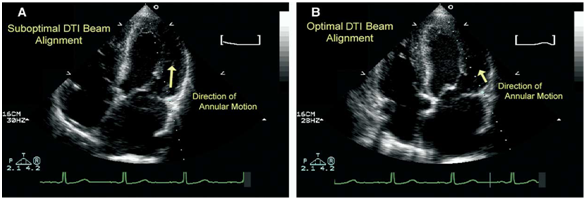

Figure 2 Suboptimal and optimal annular Doppler tissue imaging (TDI) beam alignment. A: Large angle of insonation (increased cosine) between Doppler beam and lateral annulus. As with other Doppler techniques, large insonation angle (cosine > 20 degrees) can lead to significant underestimation of annular velocities. B: in same patient, Doppler beam aligned more parallel (cosine < 20 degrees) to motion of mitral annulus. Alignment will result in more accurate recordings of annular velocities.21